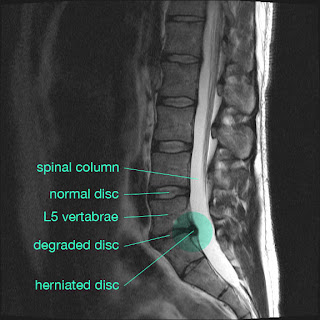

On arrival I was upgraded from the Emergency waiting room to the Fast Track assessment room and had my case referred to the Neurological department — this still took 9 hours, straight after a 17 hour journey from Bali with little sleep. I've got to know the Emergency department pretty well since then and everyone seems genuinely concerned except me. The debate is whether to operate on my severely herniated disc to remove some of it from my spinal column or whether to leave it and hope the dangerous bit of loose disc disintegrates over time. I should be in excruciating pain with the problem I have and it's only the fact that I'm not that's keeping me from the surgeons knife. I'm seeing them again on Monday for a further assessment, but they're keen, as am I, to avoid surgery if possible.

B has had severe sciatic nerve probs in the past but with good physio it can get sorted - a good cocktail of anti inflammatories also does the trick in the shorties. Is that your spine? kool picture!